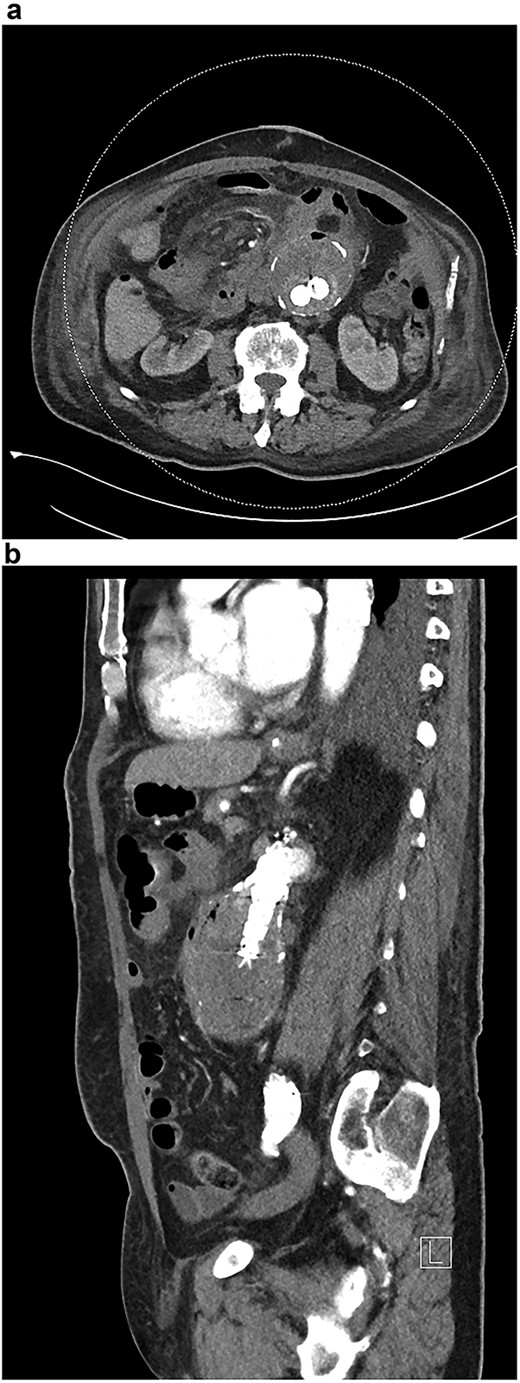

A stent with iliac limb extensions was deployed. EndoAnchors (Medtronic) were applied proximally. Final angiogram demonstrated patent renal and iliac arteries but a type 2 endoleak (Fig. 2a and b). The duodenum was accessed via midline laparotomy, with a < 1 cm defect in the posterior wall of the third part of the duodenum closed in two layers. A pedicled omental patch was interposed. Intra-operative samples grew Streptococcus gordonii and Actinomyces odontolyticus, species typically found in the oral cavity. Given the prior occupational history of the patient, Q fever serology was also requested and antibodies to the phase 1 antigen returned strongly positive, suggestive of chronic Q fever. After specialty infectious diseases input, an 18-month course of doxycycline and hydroxychloroquine and a life-long course of amoxicillin-clavulanate were commenced. He suffered post-operative delirium. On post-operative Day 10, a small amount of blood in the nasogastric tube prompted an urgent oesophagogastroduodenoscopy. The repair site had some minor ooze and was clipped. Repeat endoscopy 1 month later identified a small mucosal defect in D3 and an over-the-scope clip was applied. Six weeks after repair, outpatient blood tests demonstrated a rising white cell count. CT angiography demonstrated new gas in the aneurysmal sac (Fig. 3a).

(a) CT angiogram demonstrating new gas in the aneurysmal sac 6 weeks post-repair; (b) CT angiogram just prior to the second repair, demonstrating ongoing endoleak and continuity of the duodenum and sac; part of the duodenal clip is visible.

Six months after the index presentation, a secondary AEF was diagnosed. The patient presented similarly with syncope after massive hematemesis and a 5-day history of melena. CT angiography again demonstrated the type 2 endoleak, with active contrast extravasation into the third part of the duodenum (Fig. 3b). Once resuscitated, the patient was treated with an open explant of the stent, repair of the duodenum and bilateral axillofemoral bypass. Residual anchors from the previous EVAR remained in situ. Over two years later, he remains active and independent despite his incisional hernia, playing golf multiple times per week. His eGFR is 34 ml/minute/1.73m2. He remains on long-term anti-microbial suppression.